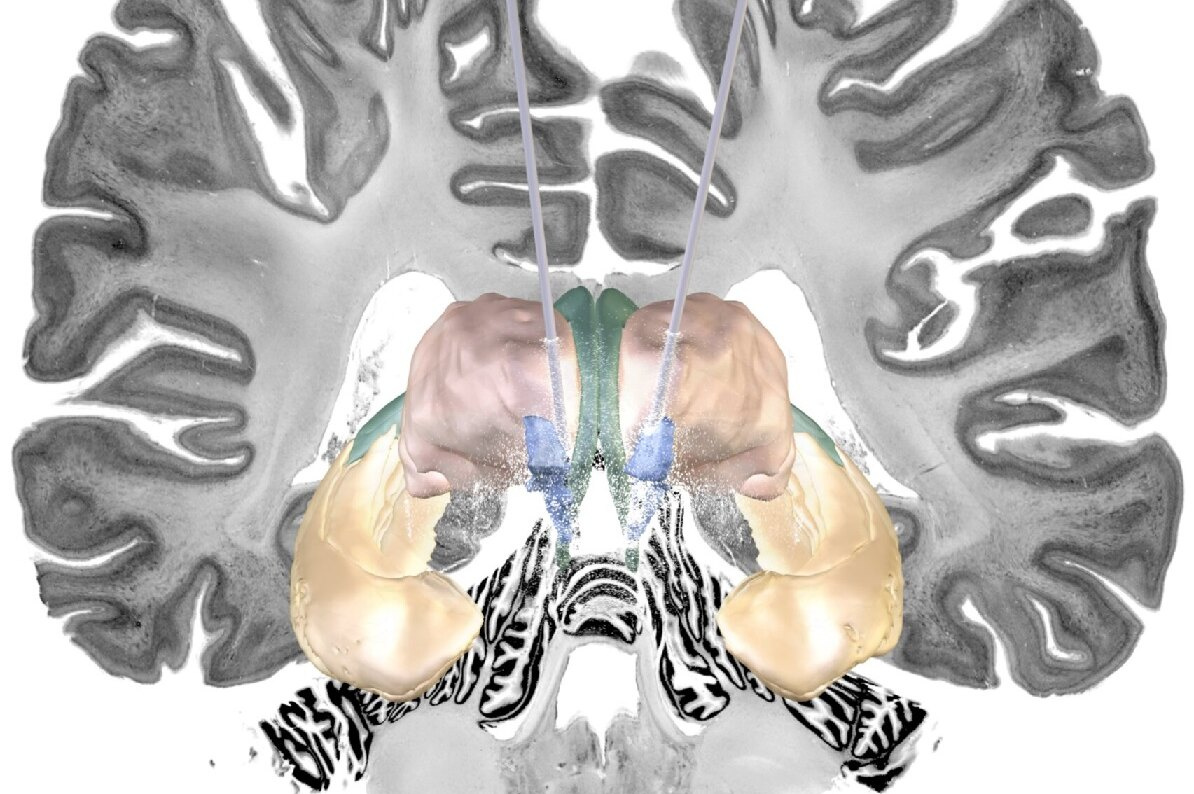

Электростимуляция при болезни Паркинсона уже стала широко распространенной клинической практикой. Но для лечение болезни Альцгеймера стимуляцию мозга еще не применяли

Глубокая стимуляция мозга (DBS) — это форма терапии, которая уже одобрена во многих странах для лечения неврологических двигательных расстройств, таких как болезнь Паркинсона и дистония, а также психоневрологических заболеваний, таких как обсессивно-компульсивное расстройство.